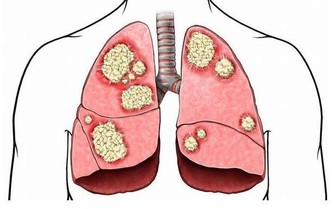

肺癌早期高危信號,警惕6種不明顯症狀!做好4點,身體會感謝你

隨著我國現代化的發展趨勢越來越快,工業污染愈加嚴重,肺癌的發病率越來越高,並有年輕化趨勢。大量資料表明,長期生活在大氣污染的環境及大量吸煙均與肺癌的發病率有著非常密切的關係,因此應該大力提倡不吸煙,並加強環境治理。

*****首先我們了解一下肺癌的早期症狀*****

一是咳嗽,最為常見的是原因不明的干咳、嗆咳等,以咳嗽為始發症狀的患者約為二分之一至三分之二。

二是胸痛,表現為不規則的鈍痛、悶痛、隱痛,部位不一定,與呼吸的關係也不確定。

三是發熱,表現為癌性發熱,是肺癌腫瘤壞死所產生的毒素引起的癌性發熱,程度不一,輕者僅有低熱,重者則有高熱,用藥後可暫時好轉,但很快又會復發。

四是反复“肺炎”,由於腫物在支氣管管腔內的佔位而引起的肺部炎症,像是重感冒的症狀,反復出現類似肺炎的症狀。

五是聲音嘶啞,患者表現為聲音嘶啞症狀,其實是肺部出現了腫瘤,縱隔淋巴結轉移,腫大的淋巴結壓迫了喉返神經引起聲帶麻痺,導致聲音嘶啞。

六是吞嚥困難,患者表現為吃東西吞嚥困難。食管和肺距離很近,所以肺部的腫瘤進展就出現了縱隔淋巴結轉移。轉移的淋巴結進一步腫大就會壓迫到食管,導致吞嚥不舒服以及吞嚥困難。

以上為肺癌最為明顯的早期症狀,對患者來說,如果能夠及早發現,及早預防,及早治療,是可以有效抵制癌細胞進一步擴散,以達到治療效果。